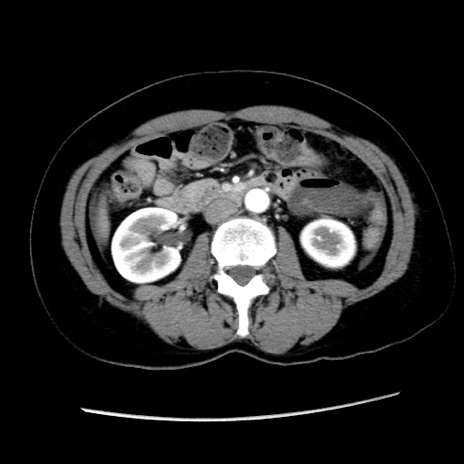

症例10(横断像)

【症例】 50歳代女性

【主訴】 腹痛

【現病歴】前日生レバーを食べた。今朝に排便あり。 昼前に突然発症の腹痛を生じ、当院救急外来を受診した。

【既往歴】 子宮筋腫にてで子宮全摘後

【身体所見】 意識清明、腹部:平坦、軟、下腹部やや左を中心に圧痛・反跳痛あり、筋性防御あり

【データ】WBC 7800、CRP 0.07